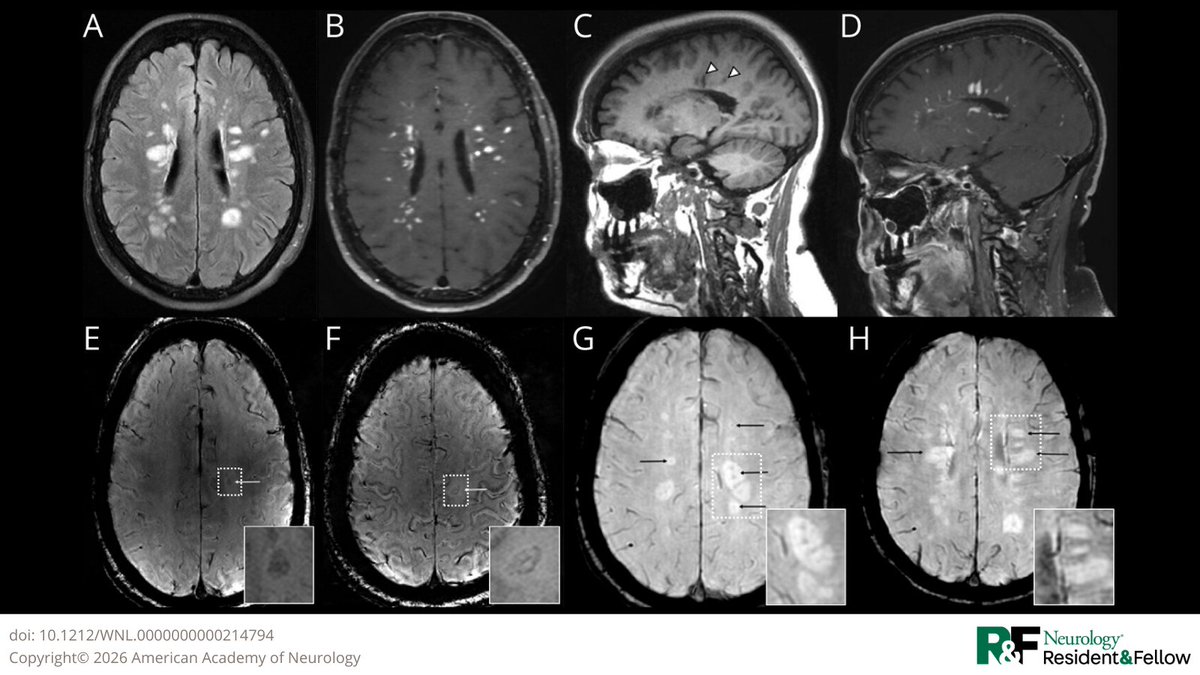

In this multicenter cohort of over 500 patients with AQP4-IgG #NMOSD, age at disease onset did not influence annualized relapse rate or time to first relapse. However, older age at onset correlated with greater long-term disability: hubs.la/Q0479mv_0